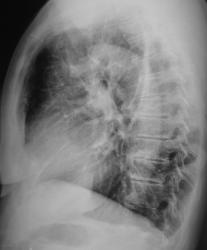

Иллюстрации 1, 2. Произведена рентгенография органов грудной полости в прямой стандартной и правой боковой проекциях. Справа на уровне 1 межреберья дифференцируется крупноочаговая тень овальной формы, от которой в сторону костальной плевры прослеживается линейный тяж. Справа регистрируется усиление и обогащение легочного рисунка. Рисунок правого корня усилен, обогащен, тень его несколько расширена.